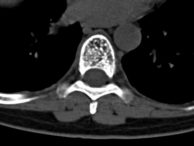

Blue Finger from Atheroembolism

Clot can arrive at the fingers from the heart or from another artery. The most common cause for clots forming in the heart is atrial fibrillation, like in the picture above. The most common artery for clots to form in is the aorta. This is called mural thrombus.